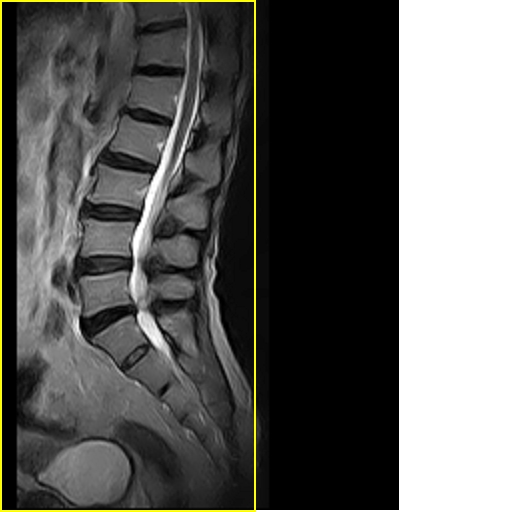

标题: MRI0859:[原创]腰椎,男,78岁,右下肢跛行两月 [打印本页]

标题: MRI0859:[原创]腰椎,男,78岁,右下肢跛行两月

男,78岁,右下肢跛行两月.

腰间盘膨出、黄韧带肥厚、可疑先天性腰椎管狭窄。

退行性病变:增生、椎间盘变性、膨出[l4-5、l5-s1 椎间盘膨出]